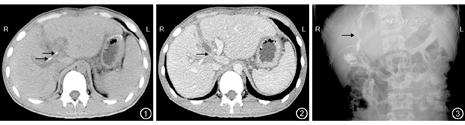

术后使用抗生素亚胺培南500 mg, 3次/d,常规保肝、输注血浆、Alb,术后第3天开始肠内营养支持,左、右肝管均有金黄色胆汁流出,胆汁量为200~ 300 mL。术后指标逐渐恢复,腹腔双套管负压引流量少,抽出内套管,接引流袋量约20 mL/ d,淡黄色,携带引流管出院,住院26 d后出院。出院31 d后因腹腔引流管引流出脓性液体,量约50 mL/ d,再次入院,无发热表现。取标本送检培养出屎肠球菌和鲍曼不动杆菌,根据药物敏感试验结果使用头孢曲松钠他唑巴坦钠抗感染,并持续腹腔冲洗。复查CT和血管造影:左右肝管及胆总管引流管在位,门静脉右支开口处狭窄(图1,图2)。胆道造影检查:左右肝管通畅,未见明显狭窄(图3)。予术后83 d拔除腹腔引流管及左右肝管内引流管,第2次住院28 d出院。术后随访至2014年12月,患者恢复良好,无并发症发生。